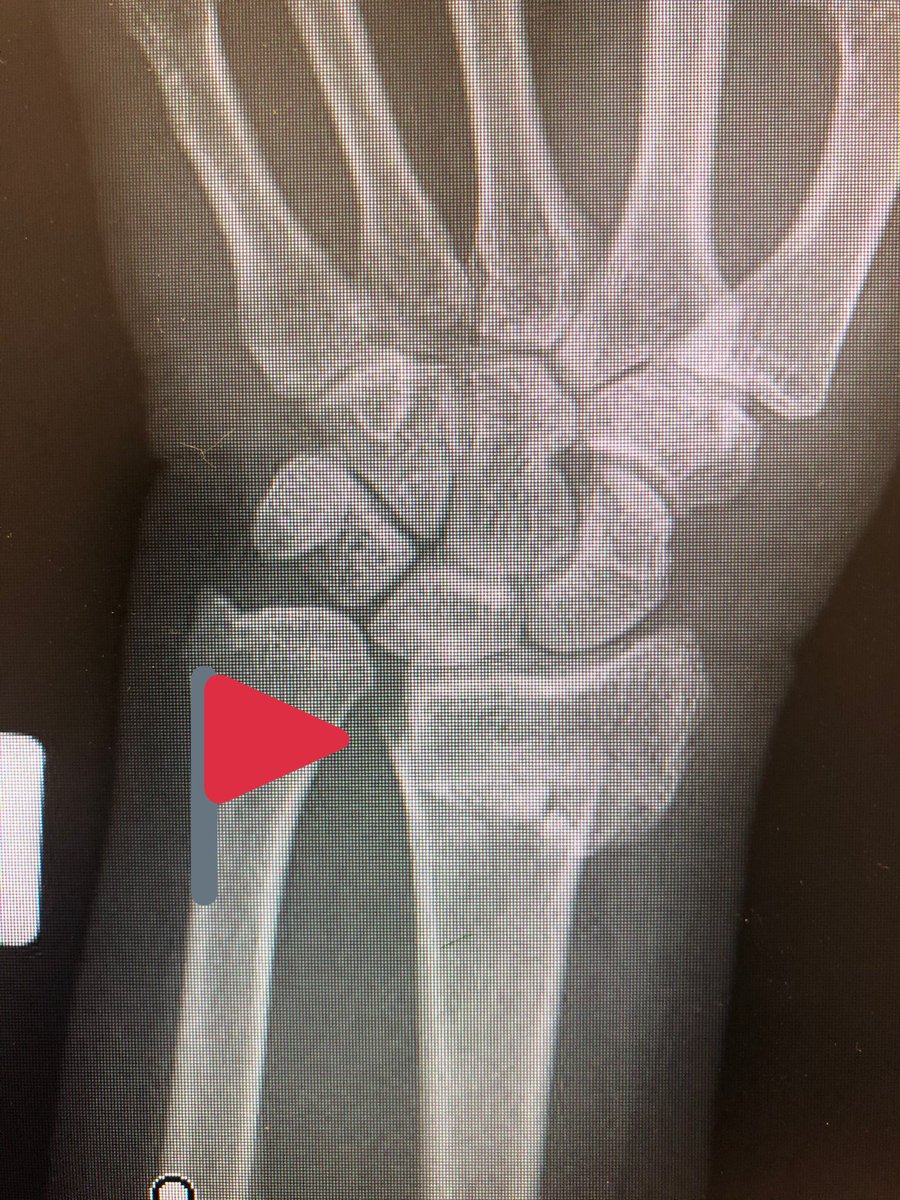

Point 3: the tangential view.

The wrist flexed ‘dorsal tangential view’ or as we locally call it ‘Lleyton Hewitt View’ is increasingly popular (published from our institutes with my colleagues too), but I find the ‘extended tangential’ or ‘DRUJ View’ more informative.

As compared to the dorsal tangential view, this DRUJ view gives better light contrast to view the dorsal rim and also additional information about the DRUJ to make sure there is no screw protrusion into the ulnar notch.